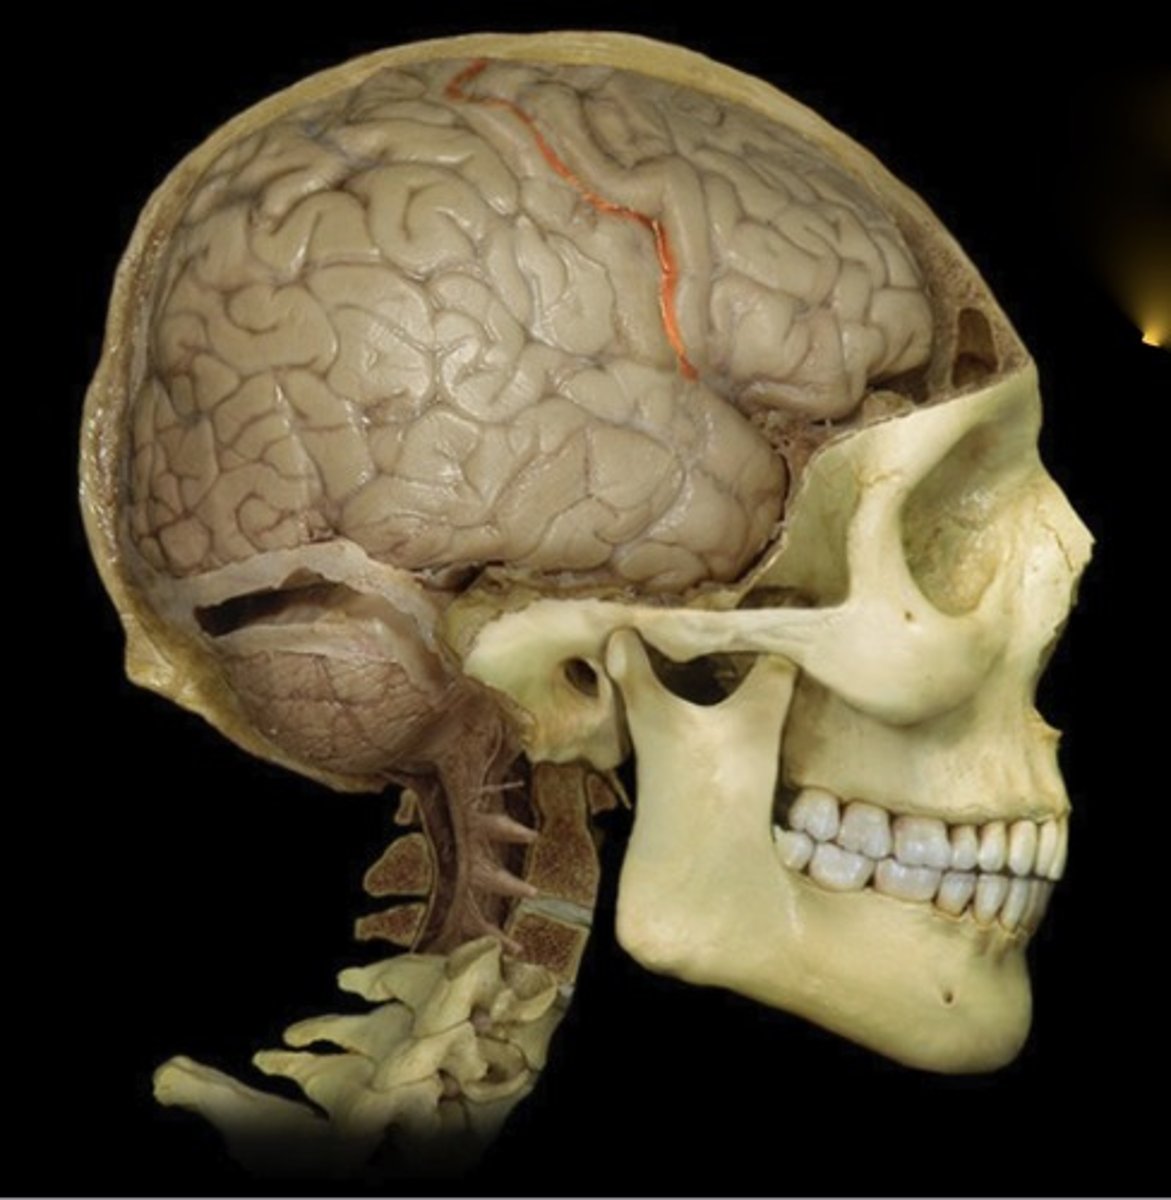

Dura Mater

Name this structure

Right cerebral hemisphere

Name this structure

Central sulcus

Name this structure

Precentral gyrus

Name this structure

Postcentral Gyrus

Name this structure

Frontal Lobe

Name this structure

Parietal Lobe

Name this structure

Temporal Lobe

Name this structure

Occipital Lobe

Name this structure

Cerebellum

Name this structure

Lateral Sulcus

Name this structure